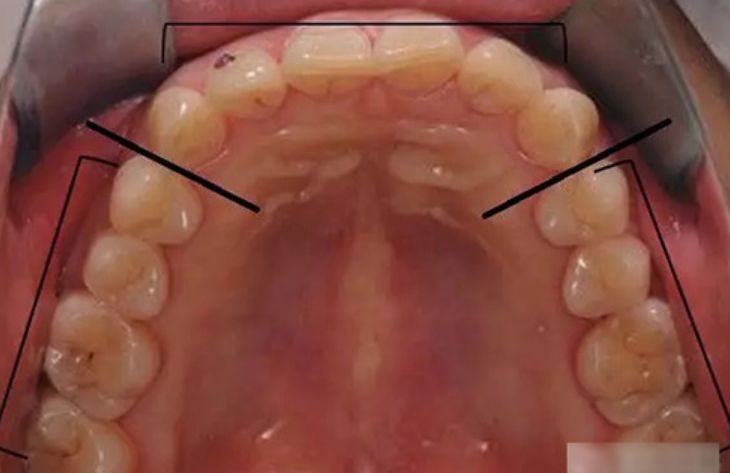

五、前牙缺失五颗或六颗,可以种植两颗或三颗架桥的方式;下颌前牙一般考虑种植两颗架桥;上颌需还要根据牙弓的弧度考虑,种植两颗或三颗,偶尔还有种植四颗的时候。

左侧弧度大,考虑种植3或4颗,右侧弧度小,考虑种植2颗或3颗